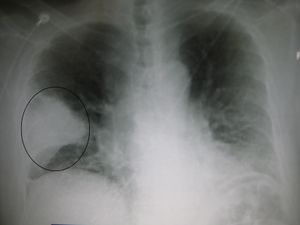

A chest X-ray showing a very prominent wedge shaped pneumonia in the right lung. | |